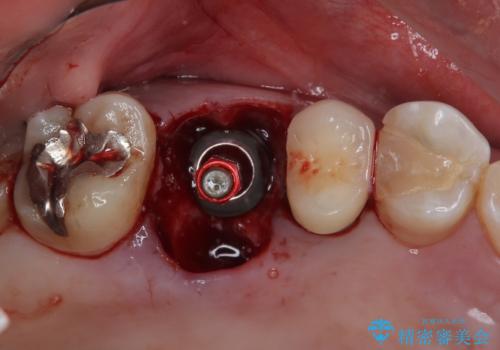

割れてしまった奥歯 1DAYインプラント治療

- 近医にて治療がなかなか進まないとのことで来院された患者様です。

詰めている材料を外したところ、目視で確認できるほど割れており、要抜歯との説明をし、インプラント治療を行うこととしました。

骨量が十分にあることが3次元CTより確認されたため、事前に仮歯を用意した上で、抜歯即時埋入インプラントによる補綴治療を行うこととしました。

来院されるまではインプラント治療を躊躇されていましたが、抜歯即時埋入により、単回の外科処置で治療が終えられることのメリットを理解され、インプラントによる補綴治療を行いました。

スムーズに治療を終えることができました。